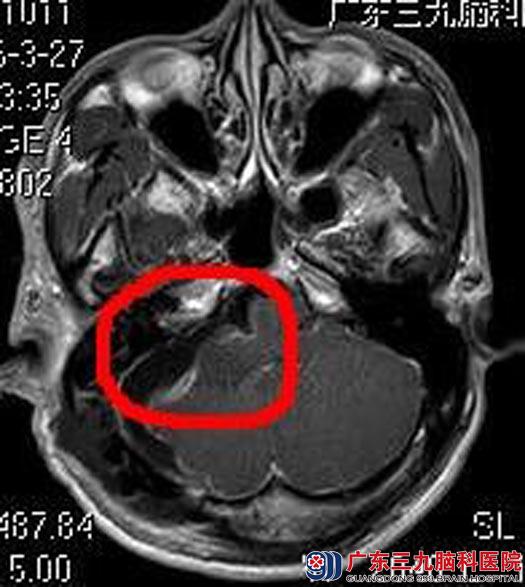

由综合神经外科鲁明主任主刀,在全麻下行右侧听神经瘤切除术,术中显微镜下见肉红色肿瘤组织,包膜完整,被小脑前下动脉包绕,质中,血供丰富,肿瘤上至三叉神经,下达后组颅神经,与面听神经及脑干明显粘连;显微镜下切除肿瘤,相邻神经、血管解剖保护满意,面听神经解剖保留,手术顺利,术后刘先生无明显后组颅神经损害症状,已满意出院。术后病理结果提示:神经鞘膜瘤。

▲术后